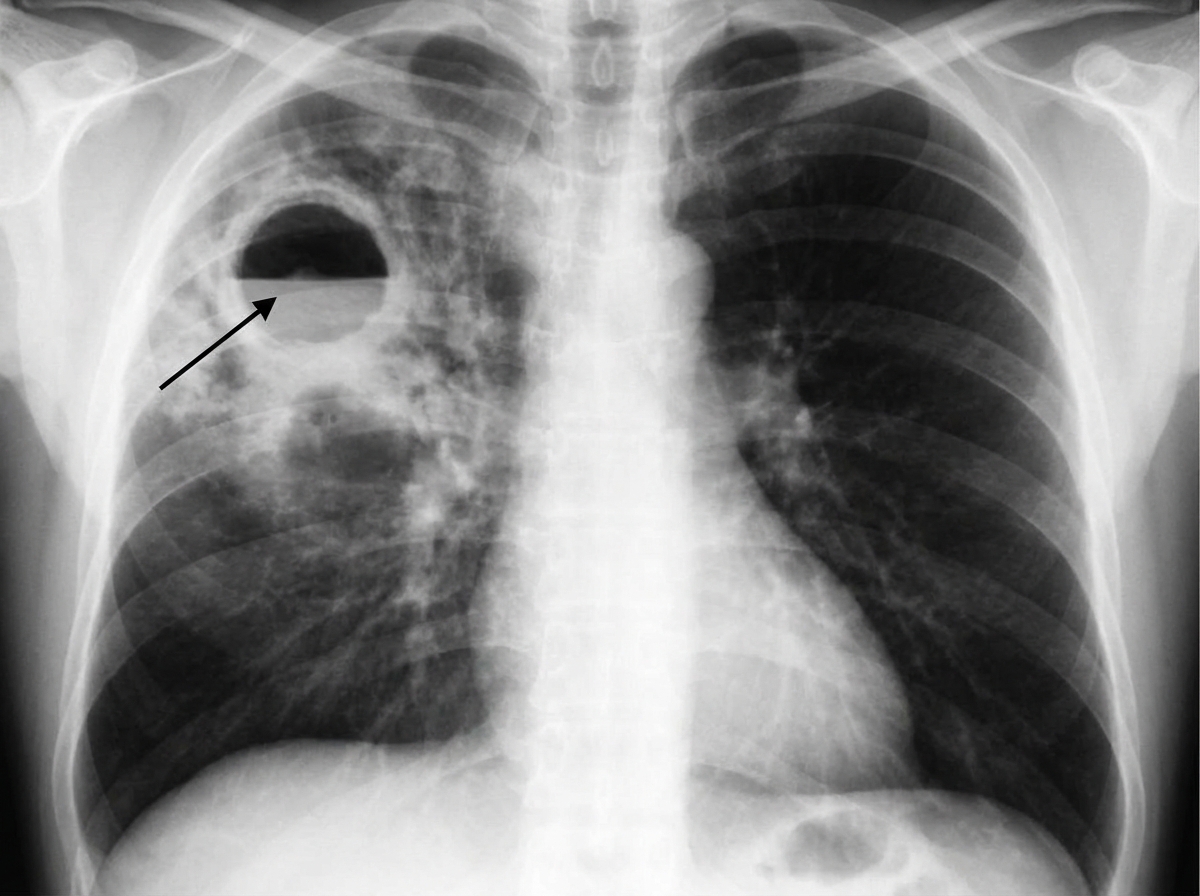

A 40-year-old man comes to the physician because of a 6-week history of increasing shortness of breath, fatigue, and fever. He has had a cough productive of foul-smelling sputum for 4 weeks. He was hospitalized for alcohol intoxication twice over the past 6 months. He has hypertension and depression. He has smoked one pack of cigarettes daily for 20 years and drinks 6 alcoholic beverages daily. Current medications include ramipril and fluoxetine. He appears malnourished. He is 185 cm (6 ft 1 in) tall and weighs 65.7 kg (145 lb); BMI is 19.1 kg/m2. His temperature is 38.3°C (100.9°F), pulse is 118/min, respirations are 24/min, and blood pressure is 147/96 mm Hg. Pulse oximetry on room air shows an oxygen saturation of 94%. Examination of the chest shows dullness to percussion over the right upper lung field. An x-ray of the chest shows a lung cavity with an air-fluid level and surrounding infiltrate in the right upper lobe of the lung. Which of the following is the most appropriate next step in management?